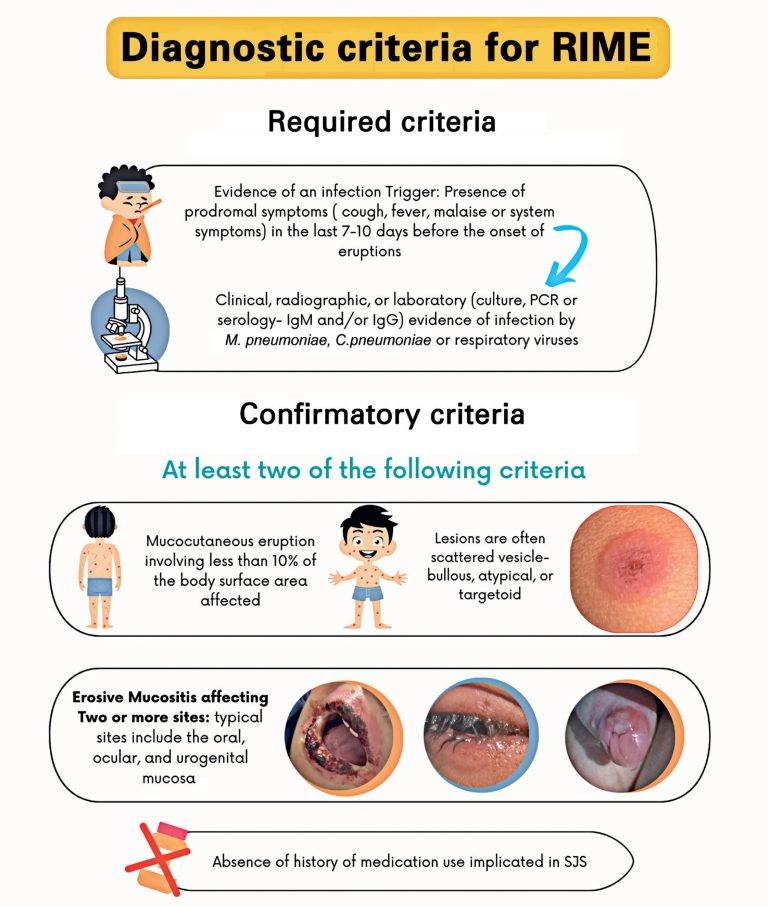

ABSTRACT Mycoplasma-induced rash and mucositis is a distinctive subset of reactive infectious mucocutaneous eruption identified in 2015 to differentiate it from other mucocutaneous disorders such as Stevens-Johnson syndrome, erythema multiforme major, and toxic epidermal necrolysis. Although its pathophysiology is not completely understood, Mycoplasma-induced rash and mucositis is characterized by polyclonal B cell proliferation, production of antibodies against Mycoplasma pneumoniae, subsequent immune complex deposition, and keratinocyte apoptosis. Clinical manifestations include scattered cutaneous lesions and severe mucositis, which predominantly affect children and […]